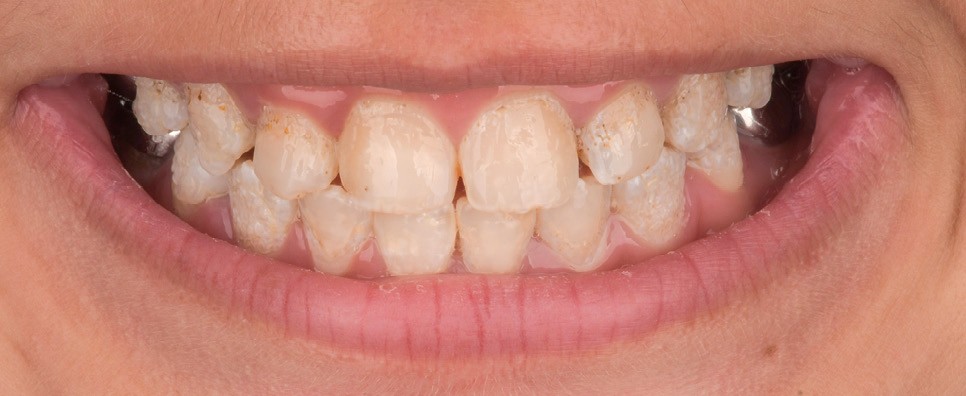

Lors de l’arrivée de la patiente, un examen clinique au fauteuil est effectué, complété par une empreinte numérique permettant l’enregistrement précis des arcades dentaires et de l’occlusion existante. Cet examen initial met en évidence une pathologie de type amélogenèse imparfaite. On note également la présence de couronnes métalliques au niveau des premières molaires, ainsi que de multiples restaurations, notamment au niveau des dernières molaires (fig. 1 à 4).

La première étape décisionnelle repose sur une analyse esthétique du visage et du sourire, réalisée à l’aide du logiciel SmileCloud. Cette analyse permet d’évaluer les proportions dentaires, la ligne du sourire et les rapports dento-labiaux. Elle confirme que le traitement vise à la fois la protection d’un émail de mauvaise qualité et l’amélioration de l’esthétique globale, avec notamment une optimisation des proportions dentaires (fig. 5 et 6).